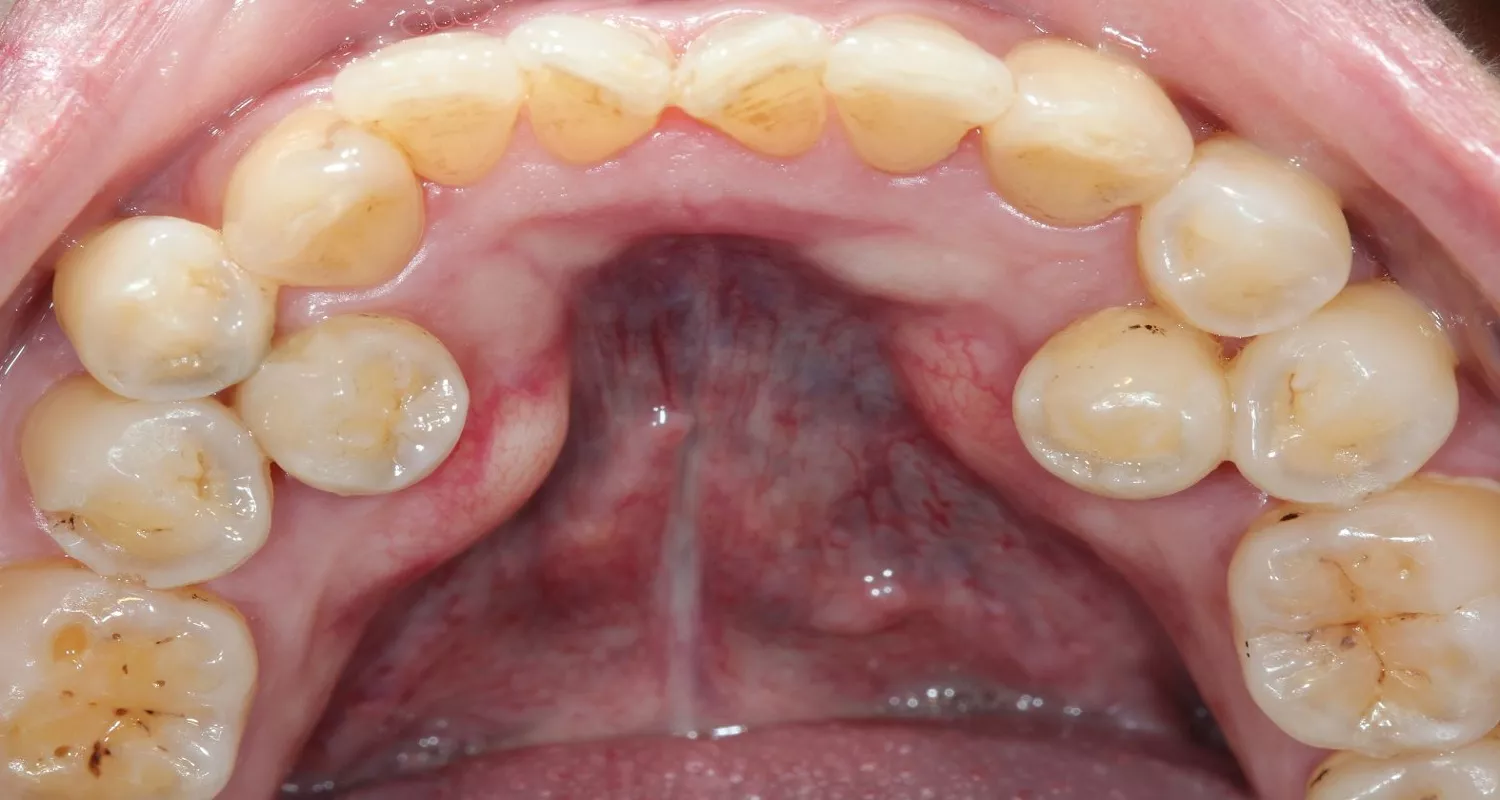

¿Cómo son los dientes extra?

No todos los dientes extra iguales. Estos son los tipos más comunes:

- Mesiodens: El más común. Es un diente pequeño que crece detrás o entre los dos dientes de enfrente (los incisivos centrales superiores).

Algunos dientes extra salen a través de la encía (erupcionados), y otros quedan atrapados dentro de la mandíbula o el maxilar (impactados). Los dientes impactados solo se pueden ver con una radiografía dental.

¿Qué siente o ve el paciente? Señales de la hiperdoncia

Muchas personas con hiperdoncia no sienten ningún dolor ni molestia, especialmente si los dientes extra están escondidos dentro del hueso. En esos casos, la única manera de descubrirlos es a través de una radiografía dental de rutina.

Sin embargo, algunos pacientes sí notan cosas como:

- Un diente o dientes que se ven raros o están en un lugar inusual

- Dientes muy juntos, apretados o torcidos

- Un espacio entre los dientes de enfrente que no se cierra solo (llamado diastema)